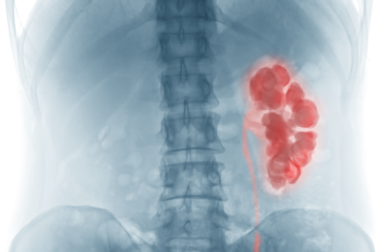

A palavra hidronefrose vem do grego. É formada pelas raízes hidro, que significa ‘água’, e nefros, que significa ‘rim’. É uma patologia que consiste no inchaço de um ou de ambos os rins. A razão é que a urina não pode ser drenada e acaba se acumulando.

A hidronefrose, como acabamos de mencionar, consiste na inflamação de um ou de ambos os rins por não conseguirem eliminar a urina que produzem. Como explica um artigo da Cleveland Clinic, essa condição pode ser crônica ou aguda.

O acúmulo de líquido nos rins pode causar a deterioração das suas funções. Esses são órgãos fundamentais para a purificação das toxinas do corpo. A insuficiência renal pode ser uma condição séria e com risco de vida.

A função renal pode ser estudada por meio de um exame de sangue ou urina. Um dos exames mais úteis para detectar a hidronefrose é o ultrassom. É seguro, simples e barato, permitindo observar se há dilatação renal ou presença de cálculos.

Os cálculos renais também podem ser vistos em radiografias. Estudos de imagem mais específicos, como tomografia computadorizada, ressonância magnética e uretrografia, são usados com frequência.